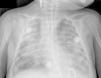

El paciente se traslada al centro de referencia con dificultad respiratoria y fiebre que no responde a tratamiento estándar, con aspirado nasofaríngeo para virus respiratorio sincitial negativo. Se orienta como insuficiencia respiratoria tipo 1 en el contexto de bronquiolitis. Se conecta a ventilación no invasiva, pero presenta un aumento del trabajo respiratorio, mala entrada de aire con abundantes subcrepitantes, elevados requerimientos de oxígeno, inestabilidad hemodinámica y condensaciones alveolares en la radiografía. Se decide intubación orotraqueal, se conecta a ventilación mecánica y se introduce soporte inotrópico con dopamina (máximo 12μg/kg/min) y, posteriormente, con adrenalina (máximo 0,12μg/kg/min). Requiere de pronación y maniobras de reclutamiento para mantener una correcta oxigenación. Durante las siguientes horas presenta empeoramiento clínico-radiológico compatible con síndrome de distrés respiratorio agudo (fig. 1). Se indica ventilación de alta frecuencia, corticoterapia y óxido nítrico inhalado. Paulatina mejoría clínica durante los siguientes días, que permite la disminución progresiva del soporte respiratorio, inotrópico y de los aportes de oxígeno hasta la extubación. Presenta fiebre intermitente y elevación de los parámetros de infección. Se inicia cefotaxima (máximo 100mg/kg/día) pero, ante mala evolución y leucopenia, se cambia a meropenem (máximo 50mg/kg/día) y vancomicina (máximo 57mg/kg/día). El hemocultivo resulta negativo y en el cultivo del lavado broncoalveolar se aíslan colonias de C. albicans; se añade fluconazol (máximo 12mg/kg/día). Se solicitan serologías para M. pneumoniae y C. pneumoniae, que resultan negativas, y reacción en cadena de la polimerasa (PCR) de virus respiratorios en aspirado traqueal, positiva para metapneumovirus. Presenta hepatomegalia y leve hipertransaminasemia con serologías para virus hepatotropos negativas, excepto IgG positiva para CMV (con IgM negativa). Se realiza un estudio de extensión en sangre, orina y aspirado traqueal; con cargas virales máximas de 1.914 copias/ml, 628.641 copias/ml y 19.142 copias/ml, respectivamente. Se solicita PCR-CMV en sangre seca (prueba del talón posnatal), que resulta negativa. Se empieza ganciclovir por vía intravenosa y, posteriormente, se continúa con valganciclovir por vía oral hasta 3 semanas. La carga viral se negativiza paulatinamente (fig. 2). Se solicitan fondo de ojo, ecografía cerebral y estudio para detección de inmunodeficiencias, siendo normales. Durante el ingreso recibe 3 transfusiones de hemoderivados, previas a la determinación de CMV.